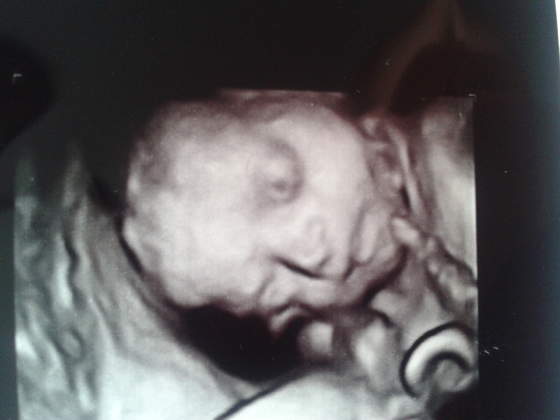

Annie- fotka

i to już!